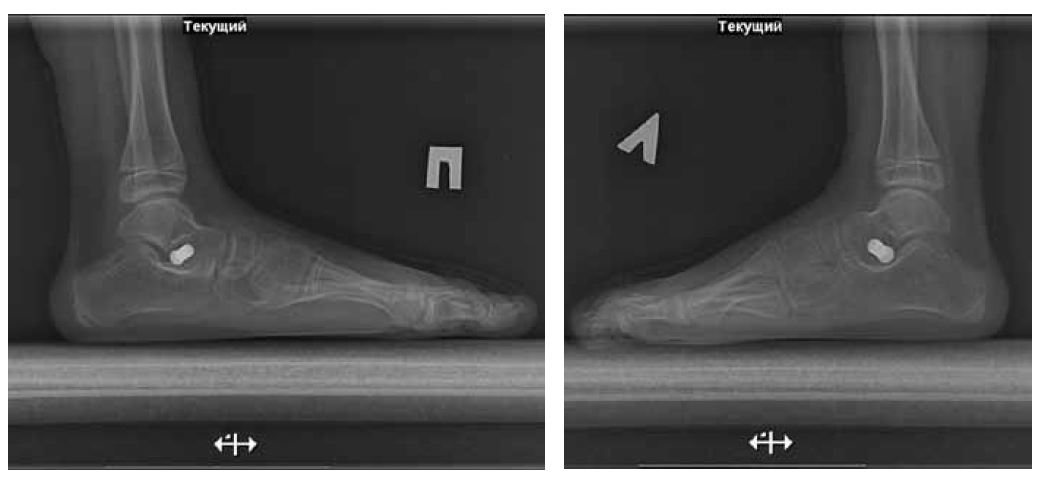

The surgery to eliminate TEPV was performed (Strayer surgery, subtalar arthroereisis, transposition with tenodesis of the anterior tibial muscle tendon under the navicular bone, grafting of the capsule of the talo-navicular joint). A cylinder plaster cast was applied from the upper third of the thigh to the tips of the toes. After 2 weeks, vertical orientation with a partial load in a plaster cast was allowed, 4 weeks after the plaster cast was removed, and a rehabilitation course was started. After 2 years and 6 months, the subtalar implants were removed (Fig. 3, 4).

Fig. 3. Radiographs of the feet under load 2 years and 6 months after surgery (lateral views)

Fig. 4. Radiographs of the feet under load 1 year after the removal of implants (lateral views)